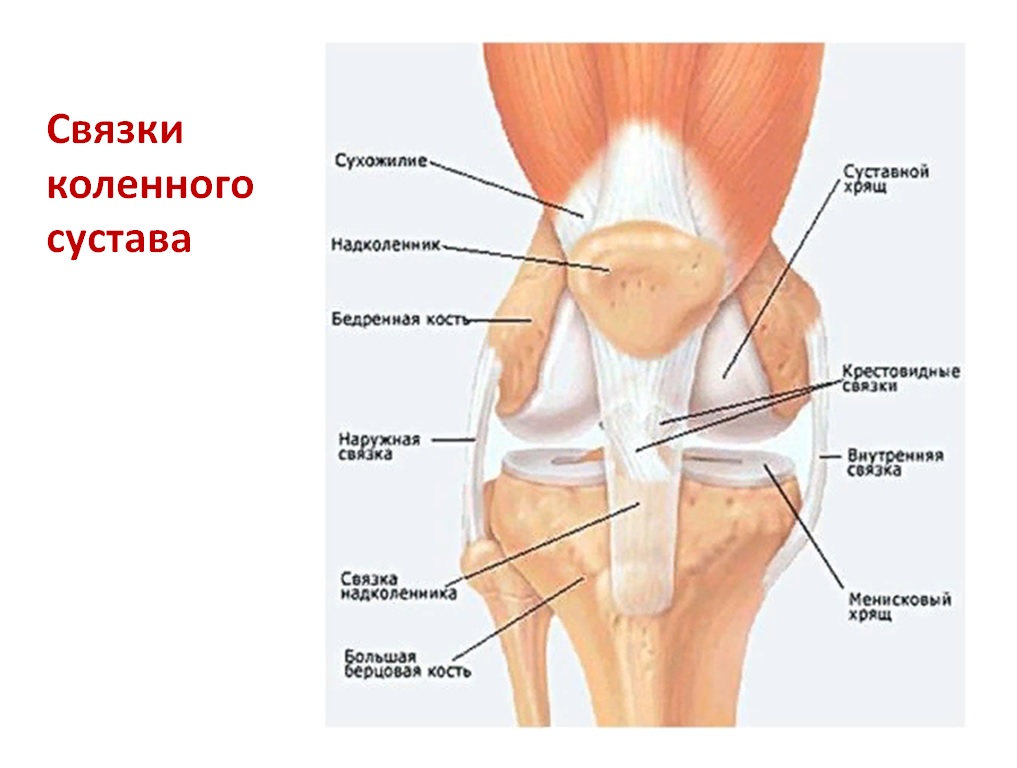

Анатомические изображения менисков и коленного сустава

Раздел: Иллюстрированные советы